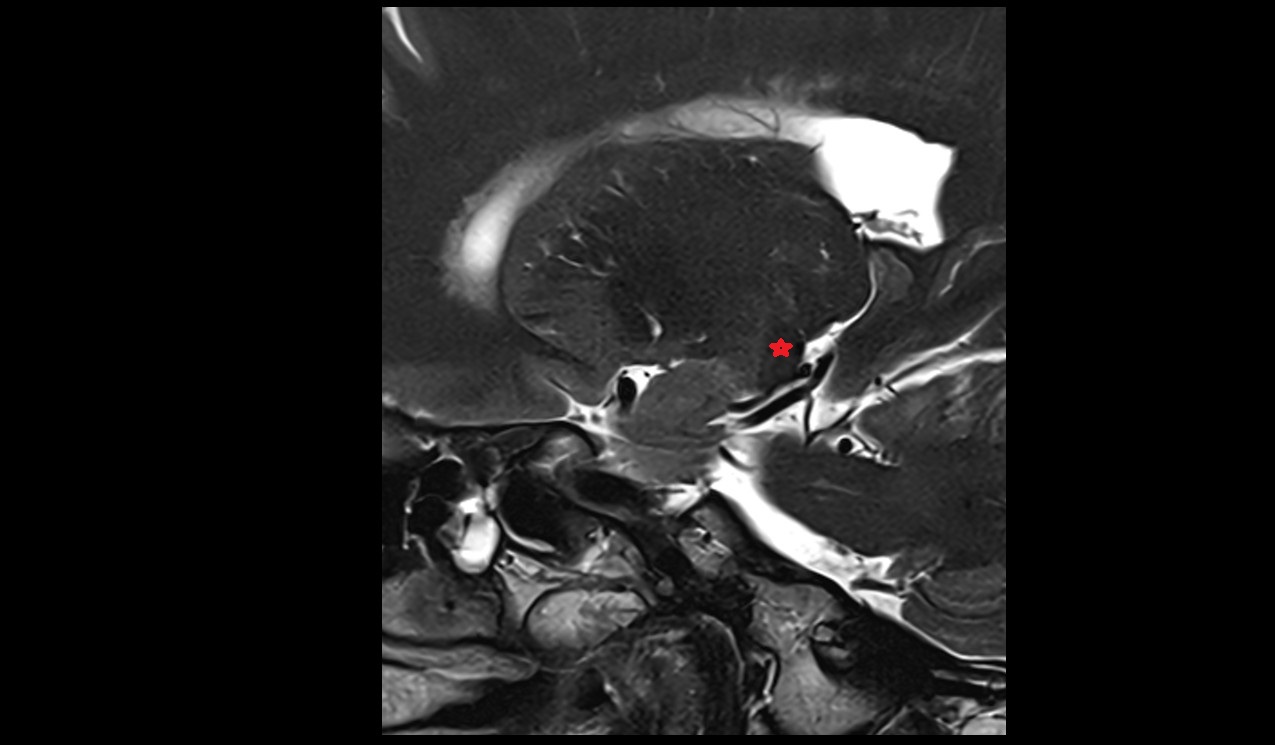

- Uterus

- Body of uterus

- Fundus of uterus

- Cervix of uterus

- Isthmus of uterus

- Endometrium of uterus

- Myometrium of uterus

- Perimetrium of uterus

- Junctional zone of uterus